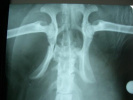

Trivet-cabinet veterinar-Cluj Napoca

Clinica ofera servicii medical-veterinare pentru toata gama de animale de companie inclusiv specii exotice. Clinica are colaborari cu pensiuni canine si specialisti in dresaj atestati de Asociatia Chinologica Romana.

Radiografii; ambulanta veterinara